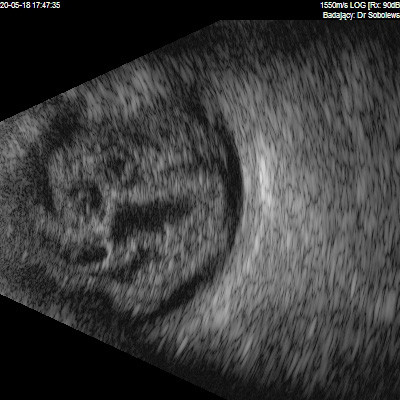

Dziwne mętów

Przedstawiane obrazy ultrasonograficzne® są oryginalne i pochodzą z mojej praktyki lekarskiej